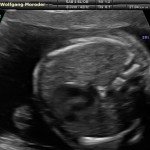

L’ecografia è una tecnica che consente di vedere gli organi del nostro corpo con l’utilizzo di onde sonore ad alta frequenza (ultrasuoni, non udibili dall’orecchio umano) che attraversano i tessuti. La sonda ecografica invia impulsi di onde sonore nel corpo. Quando le onde sonore arrivano al feto mandano degli echi: tali echi (o onde di ritorno) sono trasformati in immagini sul monitor dell’ecografo. Con l’ecografia è quindi possibile osservare in modo dettagliato il feto.

Le ragioni più comuni per cui si esegue una ecografia in gravidanza sono: determinare il numero degli embrioni o dei feti, visualizzare l’attività cardiaca fetale, determinare l’epoca di gravidanza, valutare l’anatomia e la crescita fetale, determinare la posizione del feto e della placenta

Dal secondo trimestre si misurano altre parti fetali, ed i valori di tali misure vengono confrontati con quelli delle curve di riferimento. Si può così valutare la normalità o meno della crescita fetale. Inoltre periodo si visualizzano la sede di inserzione placentare e la quantità di liquido amniotico.